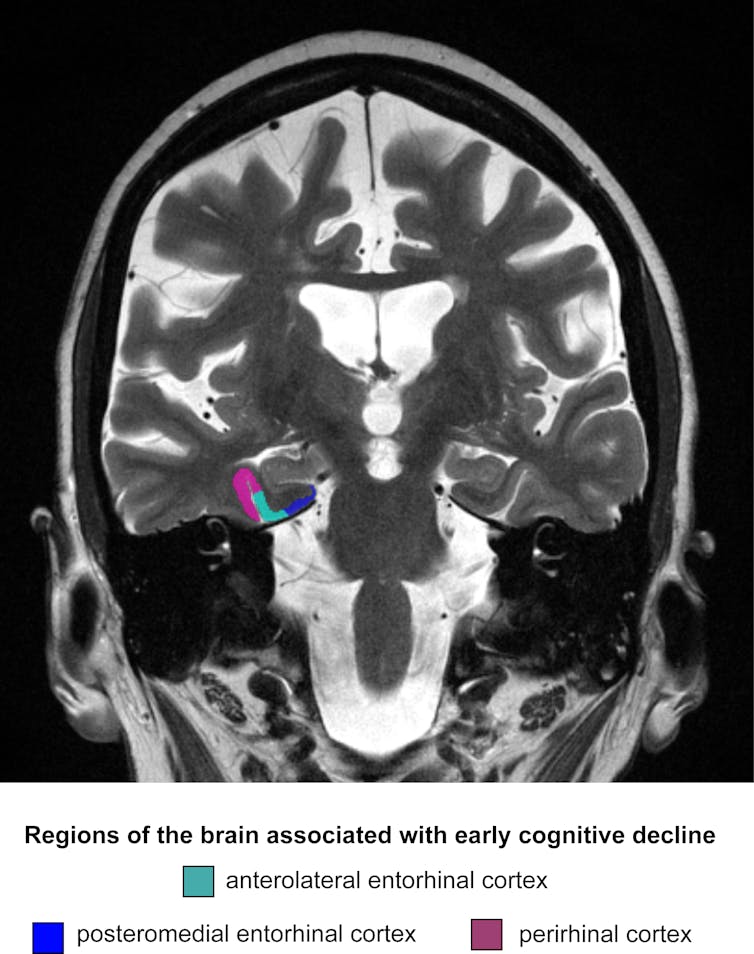

Entorhinaler cortex. Der Mediale Entorhinale Cortex sendet zeitliche Informationen an das Lernzentrum Auf diesem Weg könnte man die Gedächtnisfunktionen verbessern In einer Gehirnregion namens "Medialer Entorhinaler Cortex (MEC)" haben Säugetiere einen Plan ihrer Umgebung gespeichert. The entorhinal cortex (EC) is important in recent memory performance1 and a consistent site of neuronal pathology and volume loss in the earliest stages of Alzheimer's disease2,3 Magnetic resonance measurements of the EC size may, therefore, be of potential use for invivo diagnosis of early Alzheimer's disease The histological boundaries of the EC are not easily visible on magnetic. The entorhinal cortex is one of the brain 's most important memory centers Its main function is to relay messages to and from the hippocampus, which is viewed as one of the major sections of the brain and the epicenter of longterm memory and spatial navigation.

Entgegen früheren Definitionen dient der Assoziationskortex als sog unspezifischer Cortex nicht nur als Verbindung zwischen primären Projektionszentren (dem sog spezifischen Cortex), als Apparat mit corticocorticalen Faserverbindungen, sondern unterhält auch rückgekoppelte Verbindungen zu tiefer gelegenen Kernen des Thalamus oder des limbischen Systems. Medizin am Abend Berlin Fazit Antidepressiva effektiver einsetzen Eine internationale Studie unter KoLeitung der Universität Bern zeigt erstmals die Wirksamkeit und Verträglichkeit der am häufigsten verschriebenen Antidepressiva auf Die Erkenntnisse aus 522 klinischen Studien liefern eine bessere Grundlage, um Medikamente gegen Depression effizienter einzusetzen. Ein Nervenzelluntergang im entorhinalen Cortex ist bei Morbus Alzheimer zu beobachten und ist für die hierbei auftretenden Gedächtnisstörungen verantwortlich Neuere Untersuchungen weisen darauf hin, dass die Area entorhinalis eine wichtige Rolle bei der Selbstverortung spielt.

The entorhinal cortex (Brodmann area 28) is located in the mesial temporal lobe and acts as the interface between the hippocampus and the neocortex. “The entorhinal cortex is the golden gate to the brain’s memory mainframe,” said senior author Dr Itzhak Fried, a professor of neurosurgery at the David Geffen School of Medicine at UCLA “Every visual and sensory experience that we eventually commit to memory funnels through that doorway to the hippocampus. Nach Entorhinaler Cortex Läsion (ECL), bei der die Durchtrennung des Tractus perforans (PP) eine Denervation des Hippocampus bewirkt, kommt es zu einem langanhaltenden Verlust von Myelin.